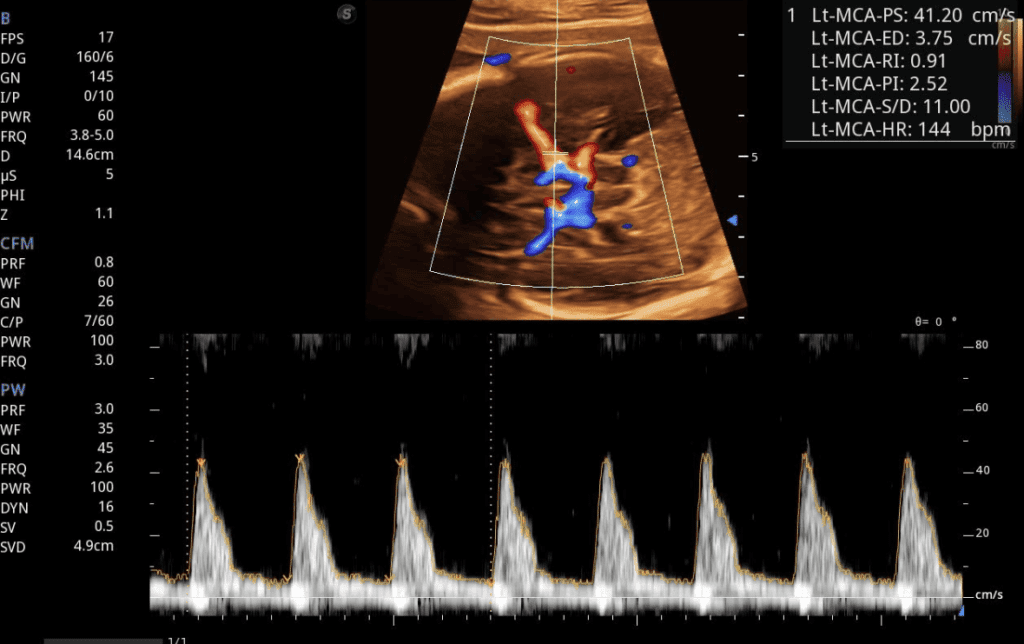

Doppler Fetal

Evalúa el flujo sanguíneo del bebé durante el embarazo, monitoreando la circulación umbilical y cerebral para detectar posibles complicaciones y asegurar el bienestar fetal.

Perfil Hemodinámico

Estudio completo del flujo sanguíneo fetal que incluye arteria umbilical, cerebral media y ductus venoso para una evaluación integral del bienestar fetal.